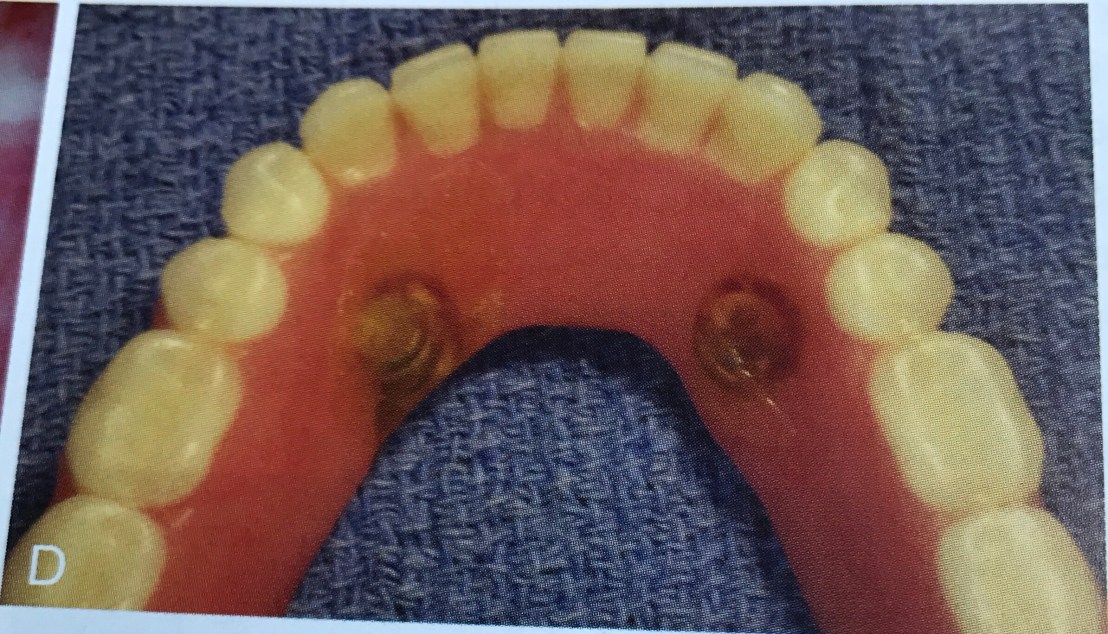

แสดง Ideal Implant placement สำหรับ Removable Prosthesis (Occlusal view)